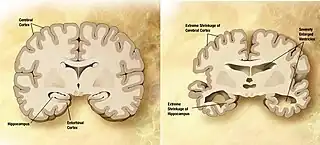

Impact from disease

Neurodegenerative diseases and psychological disorders can affect various characteristics of curiosity. For example Alzheimer's disease's effects on memory or depression affect motivation and reward. Alzheimer's is a neurodegenerative disease that degrades memory. Depression is a mood disorder that is characterized by a lack of interest in one's environment and feelings of sadness or hopelessness. A lack of curiosity for novel stimuli might be a predictor for these and other illnesses.[24]